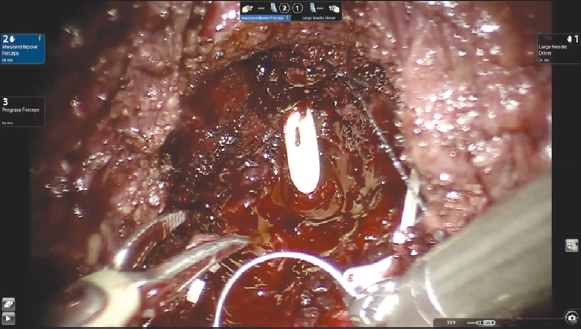

Вскрытие париетальной брюшины в проекции шейки мочевого пузыря. Операция выполняется трансперитонеально, расположение роботических троакаров повторяет таковое при традиционном доступе. Ассистентские 12- или 5-миллиметровые порты также устанавливаются стандартно: параректально справа на 2–3 см выше оптического порта и на 6–8 см латерально от правого роботического порта соответственно. На первом этапе происходит вскрытие париетальной брюшины. В отличие от традиционного доступа, инцизия производится в проекции шейки мочевого пузыря, а не его верхушки. Для лучшей визуализации третьим роботическим инструментом осуществляется тракция задней стенки мочевого пузыря вверх. Выделение семявыносящих протоков и семенных пузырьков (рис. 1). Этот этап операции выполняется сразу после вскрытия париетальной брюшины. Техника диссекции семявыносящих протоков и семенных пузырьков не отличается от стандартной. Основным фактором, обеспечивающим техническую сложность этого этапа, является небольшой объем операционного поля и невозможность выполнения широких тракций семенных пузырьков и самой предстательной железы, которая на данном этапе остается выделенной лишь на небольшой поверхности ее основания. Выделение задней поверхности простаты и сосудисто-нервных пучков (рис. 2), как и при традиционном доступе, происходит после этапа выделения семенных пузырьков. Уровень нервосбережения определяется на основании стадии опухолевого процесса. Для доступа к заднелатеральным отделам предстательной железы выполняется частичная латеральная диссекция пузырно-простатических мышечных волокон. Диссекция шейки мочевого пузыря (рис. 3) выполняется в направлении снизу вверх и является одним из самых сложных шагов этой операции. На этом этапе в наибольшей степени проявляется преимущество свободно изгибающихся на концах роботических инструментов. Для лучшей визуализации используется развернутая наверх (30°) оптика. Шейка мочевого пузыря вскрывается по задней поверхности, уретральный катетер извлекается, после чего рассекается передняя ее поверхность. Диссекция дорзального сосудистого комплекса производится тупым и острым путем без предварительного прошивания и перевязывания. После выделения верхушки простаты железа отсекается от уретры. На этом этапе при необходимости производится прошивание элементов дорзального комплекса. На рис. 4 представлено ложе удаленной предстательной железы. Наложение пузырно-уретрального анастомоза (рис. 5) начинается с передней его стенки на 12 ч условного циферблата. Анастомоз выполняется с использованием самозатягивающихся нитей. Сложность этого этапа обусловлена, в основном, непривычной визуализацией. Ввиду того, что мобилизация мочевого пузыря не производилась, сопоставление слизистой уретры и мочевого пузыря происходит без видимого натяжения, поэтому усиления соустья с помощью дополнительной реконструкции не требуется. При необходимости выполняется задняя пластика шейки мочевого пузыря. Последним этапом производится установка дренажа к зоне анастомоза и ушивание париетальной брюшины.

Рис. 2. Выделение задней поверхности предстательной железы и сосудисто-нервных пучков

Fig. 2. Isolation of the posterior surface of the prostate gland and neurovascular bundles